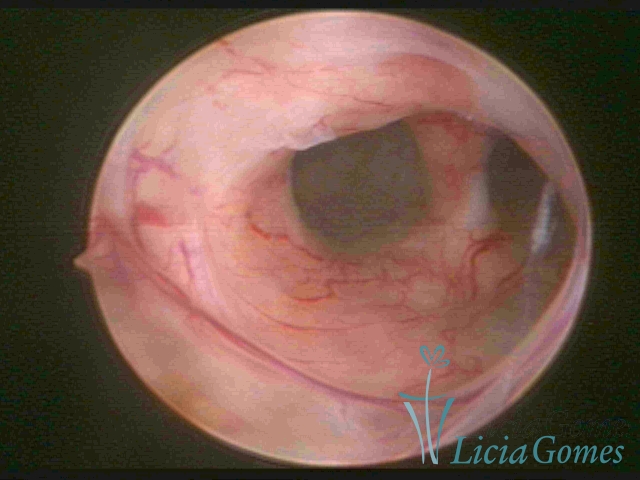

Septate uterus

It probably occurs by the lack of resorption on the middle line, in the merge of Müllerian ducts. The uterus is divided by a partial or total septum which is viewed as a crossbar, not covered by endometrium, which not bleeds when sectioned.

Complete septum when it occupies the whole extension of the cavity, dividing it into two hemicavities.

When this septum occupies only a part of the extension of the uterine cavity, it is considered as incomplete.